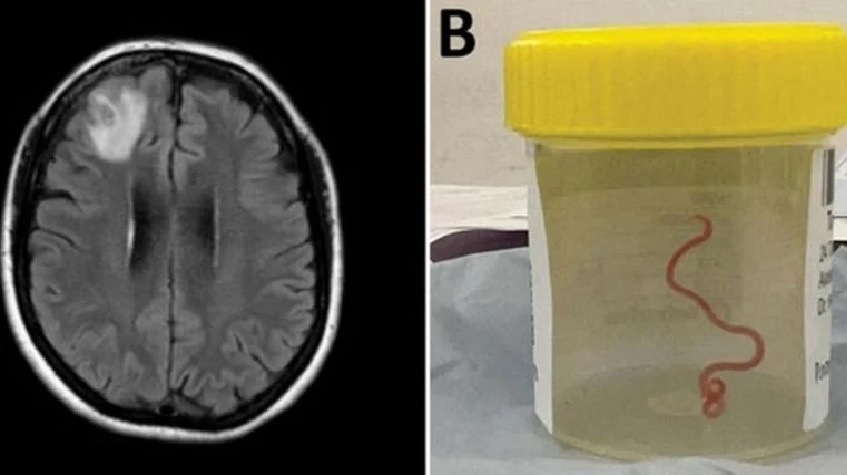

En un caso nunca antes documentado en el mundo, científicos informaron que encontraron un gusano vivo de 8 cm en el cerebro de una mujer en Australia.

Los médicos dijeron que el parásito rojo pudo haber estado vivo en el cerebro de la mujer hasta por dos meses.

"Todos en ese quirófano sufrieron el shock de su vida cuando [la cirujana] tomó unas pinzas para detectar una anormalidad y la anormalidad resultó ser un gusano vivo, de color rojo claro, de 8 cm, que se retorcía", dijo la doctora Sanjaya Senanayake, especialista en enfermedades infecciosas del Hospital de Canberra.

FOTO: ANU

UN ESCÁNER CEREBRAL Y EL NEMATODO EXTRAÍDO EN UN FRASCO DE MUESTRAS,